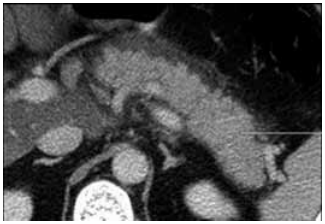

Analise o caso clínico a seguir para responder à questão:

Paciente do sexo masculino, de 52 anos, IMC igual a

41 kg/m2, portador de diabetes mellitus tipo 2, em uso de

semaglutida 2,4 mg/semana há três meses e rosuvastatina

20 mg/dia, é admitido na UTI com dor epigástrica intensa

irradiada para dorso, taquipneia e oligúria há dezoito horas.

Relata náuseas e vômitos persistentes, sem etilismo recente

há 32 horas. Ao exame físico: PA: 88 × 54 mmHg; FC: 124 bpm;

FR: 32 irpm; SpO2

91% em O2

nasal: 3 L/min; T: 38,7 °C.

Abdome distendido, doloroso difusamente, sem defesa

peritoneal franca. Exames laboratoriais iniciais: leucócitos:

22.300/mm3; amilase: 1.040 U/L; lipase: 1.350 U/L; creatinina: 2,2 mg/dL (prévia: 0,9 mg/dL); lactato: 3,8 mmol/L;

PCR: 42 mg/dL; triglicerídeos: 210 mg/dL; AST/ALT: discretamente elevadas; pH: 7,28; HCO3–: 18; PaO2: 62 mmHg;

FiO2: 0,4. TC de abdome com contraste mostrado a seguir:

(Arquivo pessoal; imagem usada com autorização)